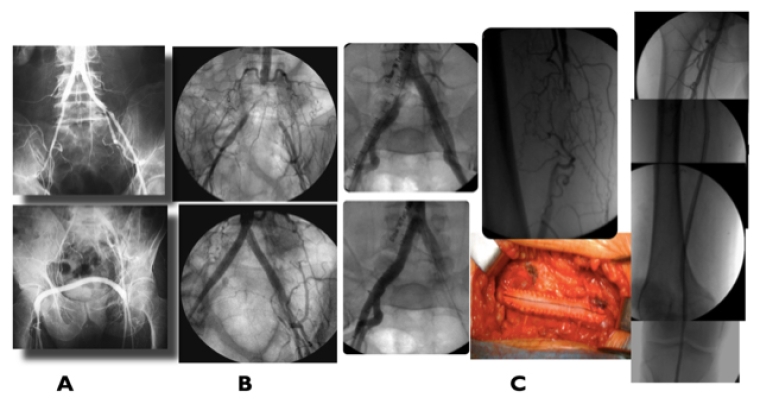

Open bypass surgery for extensive and calcified occlusions in patients with average surgical risk and a suitable autologous vein (Table 2) continues to be the preferred choice for revascularisation with an inflow source from a distal popliteal artery. In diabetic patients, a patent segment of a pedal or plantar artery can be targeted for a bypass (Figure 3, A and B). Prosthetic grafts with adjuvant techniques such as arteriovenous fistula or venous cuffs at the distal anastomosis have been used, but with poor long-term durability.

Figure 3. Revascularisation for infra-popliteal disease

A) Diabetic patient with CLTI toe amputations due to extensive long occlusions in all infrapopliteal arteries and patent dorsalis pedis (DP) artery treated by distal popliteal–DP vein bypass. B) Patient with CLTI due to distal infrapopliteal occlusions associated with chronic embolisation from a popliteal aneurysm successfully treated by SFA–plantar artery vein bypass.

Identification of the TAP, defined as the best direct flow route to the leg and foot arteries, is paramount. It may require a hybrid procedure combining a bypass with distal infrapopliteal ER or extending the vein bypass directly to a patent crural artery connected with the foot arterial vasculature (Figure 2, A and B).

Figure 2. Femoropopliteal revascularisation

A) Diabetic patient with CLTI with extensive femoropopliteal complete occlusion + leg disease, run-off 1 vessel. Successful femoro-posterior tibial vein bypass. B) Femoropopliteal vein bypass plus popliteal/tibio-peroneal trunk PBA for CLTI.